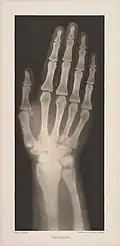

Autoři fotografií: Josef Maria Eder a Eduard Valenta

Ženská ruka -